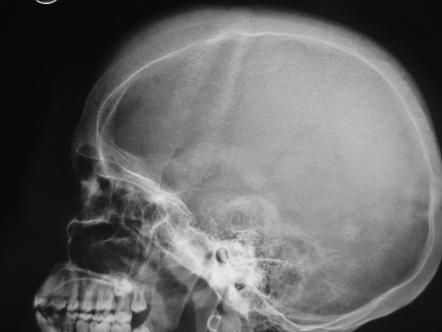

Hair on end sign is a radiological finding on skull radiograph. This classical picture is attributed to: - thalassemia major - iron deficiency anemia - sickle cell disease - hereditary spherocytosis Reference: https://radiopaedia.org/articles/hair-on-end-sign-mnemonic Image via: https://radiopaedia.org/articles/hair-on-end-sign-mnemonic